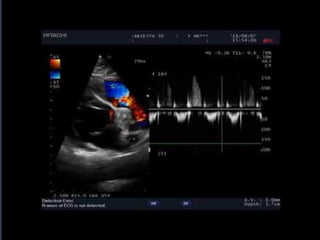

e a data da realização. A presença de outras funcionalidades, como

Doppler colorido, Modo - M e Doppler espectral não são necessários

para a realização do exame, assim como a presença de ECG.